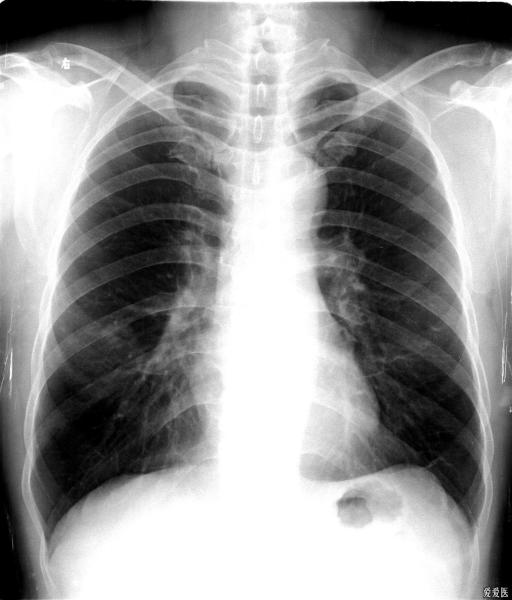

右肺中叶综合征

右肺中叶综合征的鉴别诊断

右肺中叶改变

右肺上叶切除术后炎症导致右肺中叶综合征一例

右肺中叶不张的成因(肺不张影像表现)(10)